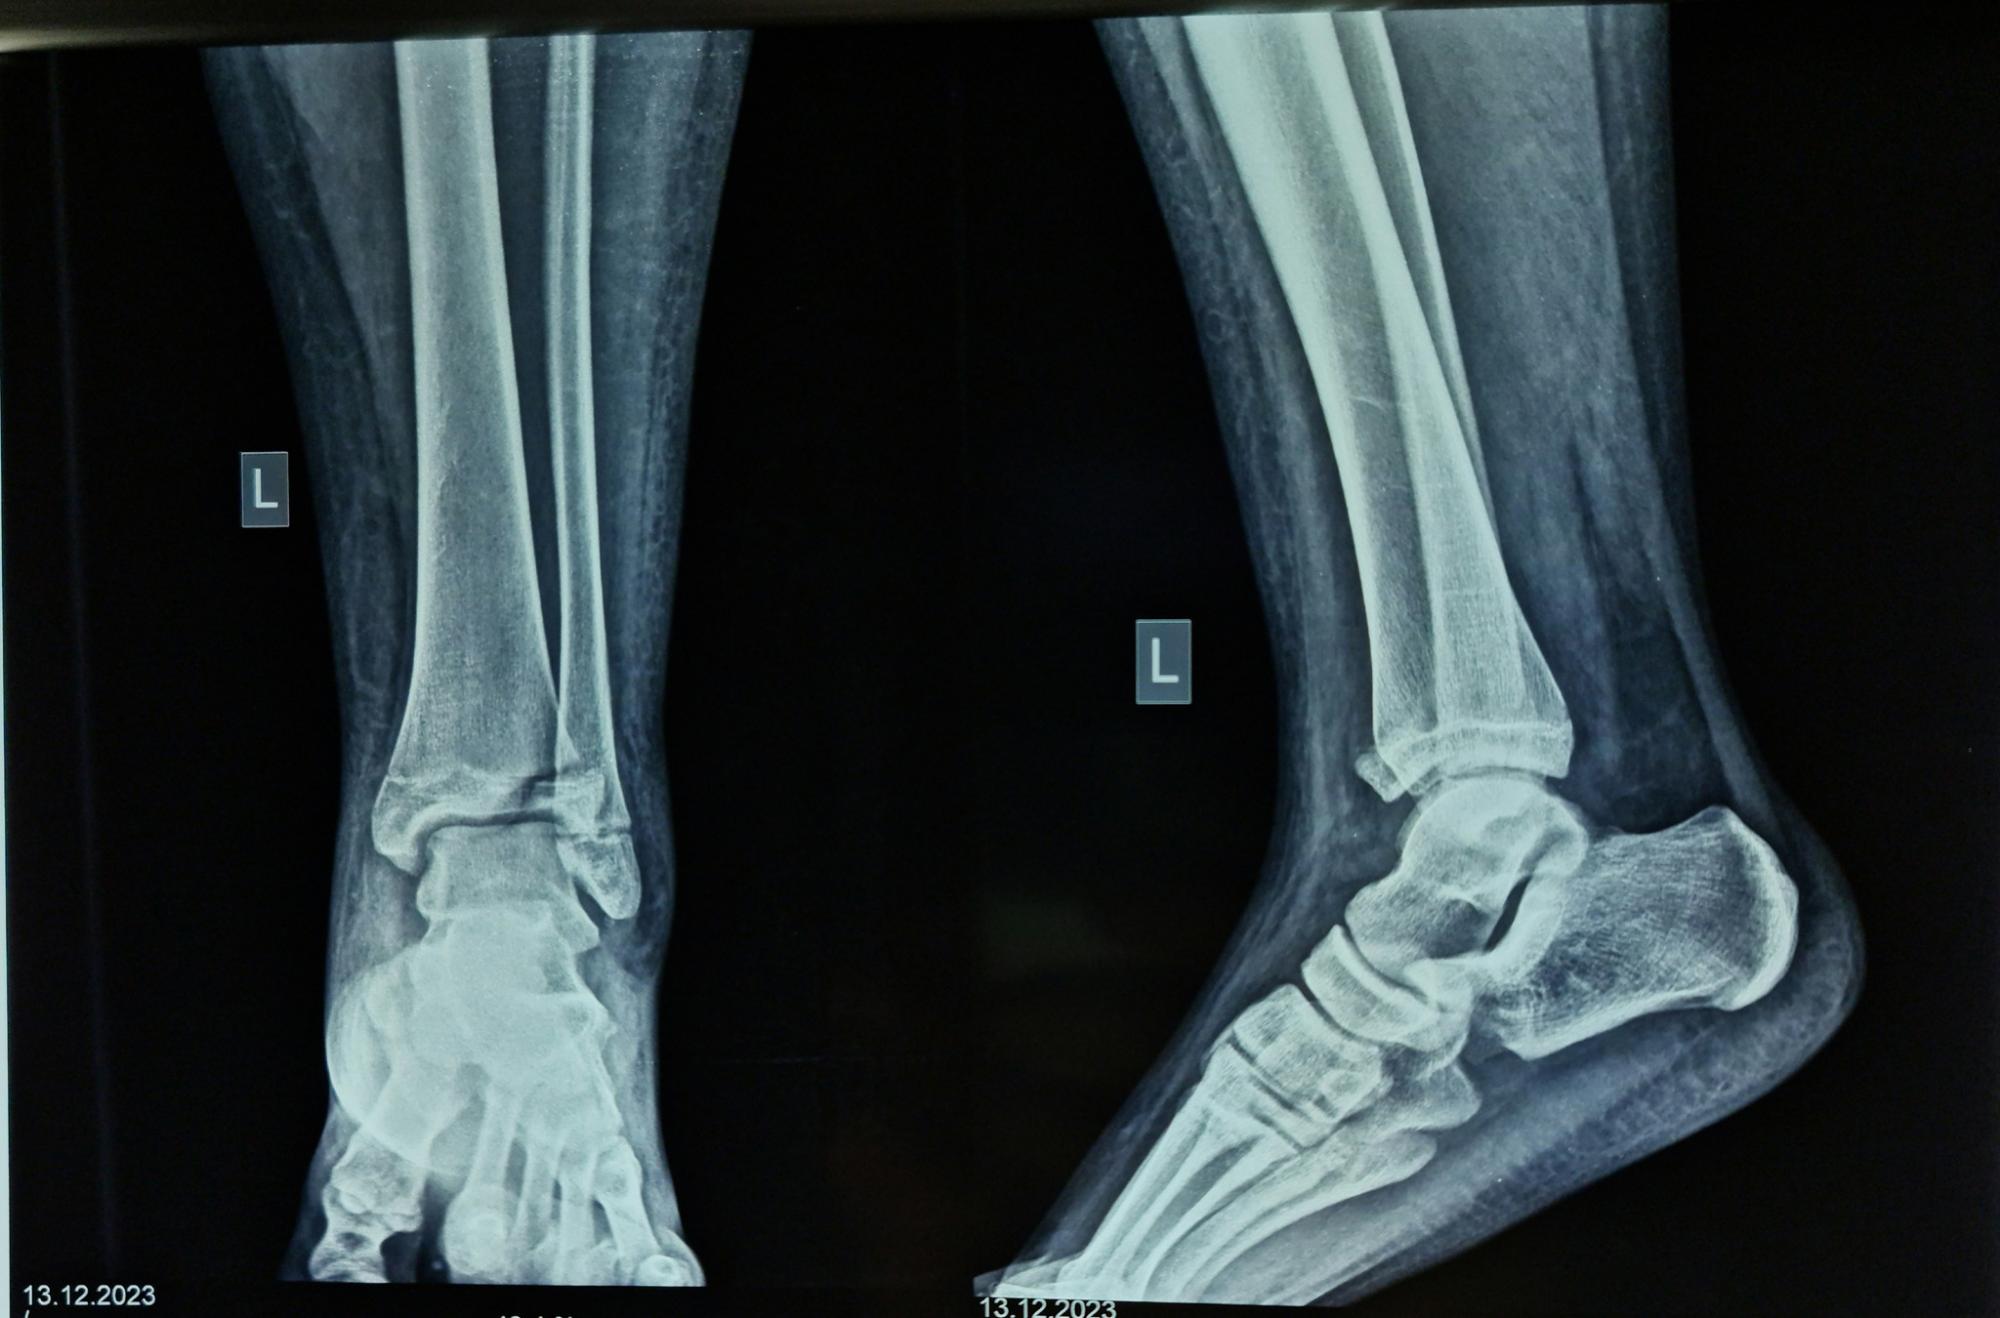

Пацієнтку госпіталізували в ортопедо-травматологічний центр лікарні з переломом великогомілкової кістки, якому було вже два тижні. За допомогою рентгенографії вдалося визначити, що це був рідкісний перелом Тілло.

За словами медиків, цей вид перелому виникає внаслідок зайвої зовнішньої ротації в гомілковостопному суглобі. Він призводить не тільки до деформації кістки, а й до пошкодження передньо-нижньої великогомілкової зв’язки.

Перелом Тілло (фото: facebook.com/RivneODL)